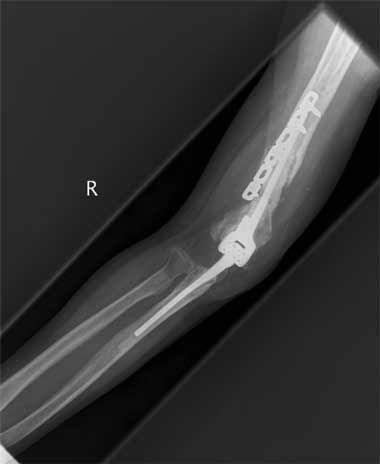

Sideswipe injuries (syn. baby car injuries, traffic elbow injury) are sustained when a patient while travelling in a vehicle with elbow resting on the window is hit by a coming object or a vehicle on the road. 1. These injuries constitute a subgroup of complex elbow trauma.